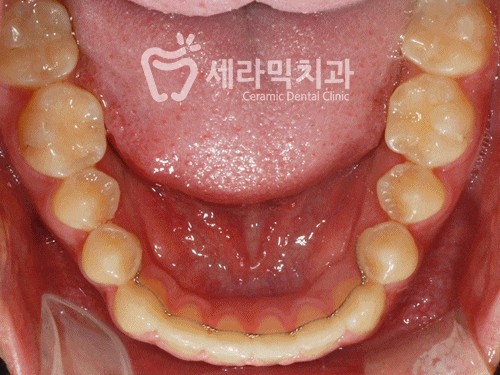

【 벌어진치아 치아교정전후 하악 】

11개월만에 벌어졌던 치아가 교정되면서

치열이 깔끔하고 건강해졌습니다.